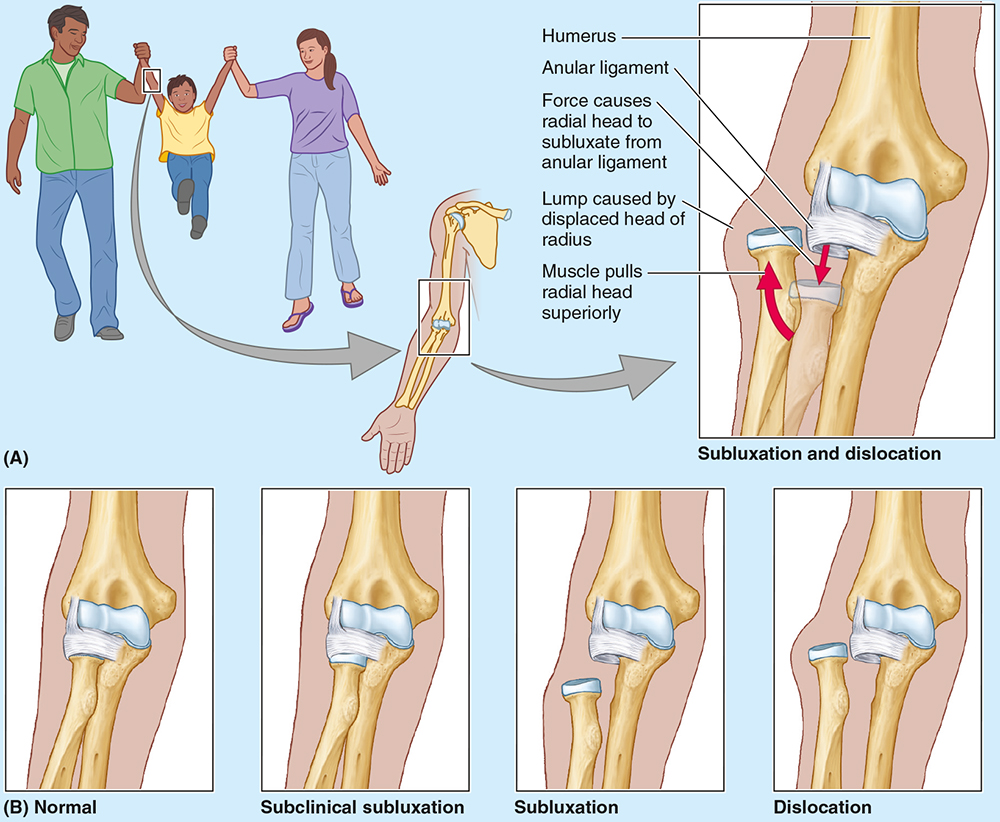

Nursemaid’s elbow is a common injury in preschool children, especially girls, caused by sudden pulling of the pronated forearm (e.g., lifting a child). The _________ tear causes subluxation of the radial head.

annular ligament

Nursemaid’s elbow is a common injury in preschool children, especially girls, caused by sudden pulling of the pronated forearm (e.g., lifting a child). The annular ligament tear causes __________ of the radial head.

subluxation

Treatment of nursemaid’s elbow involves?

Treatment involves supination with elbow flexion; healing occurs with sling use for 2 weeks.

The elbow is stabilized by the ulnar and radial collateral ligaments, whereas the _____________ holds the radius against the ulna for rotation.